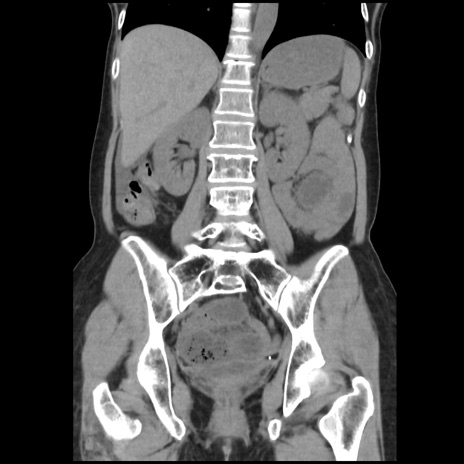

症例32(冠状断像)

【症例】40歳代 女性

【主訴】上腹部痛、嘔気・嘔吐

【現病歴】約9時間前頃から急に上腹部痛、嘔気、嘔吐が出現。改善しないため救急要請。

【既往歴】子宮頚癌(広汎子宮全摘術、放射線療法)、腸閉塞

【身体所見】腹部:平坦、軟、腸雑音亢進、上腹部を中心に腹部全体に圧痛あり。

【データ】WBC 8400、CRP 0.03